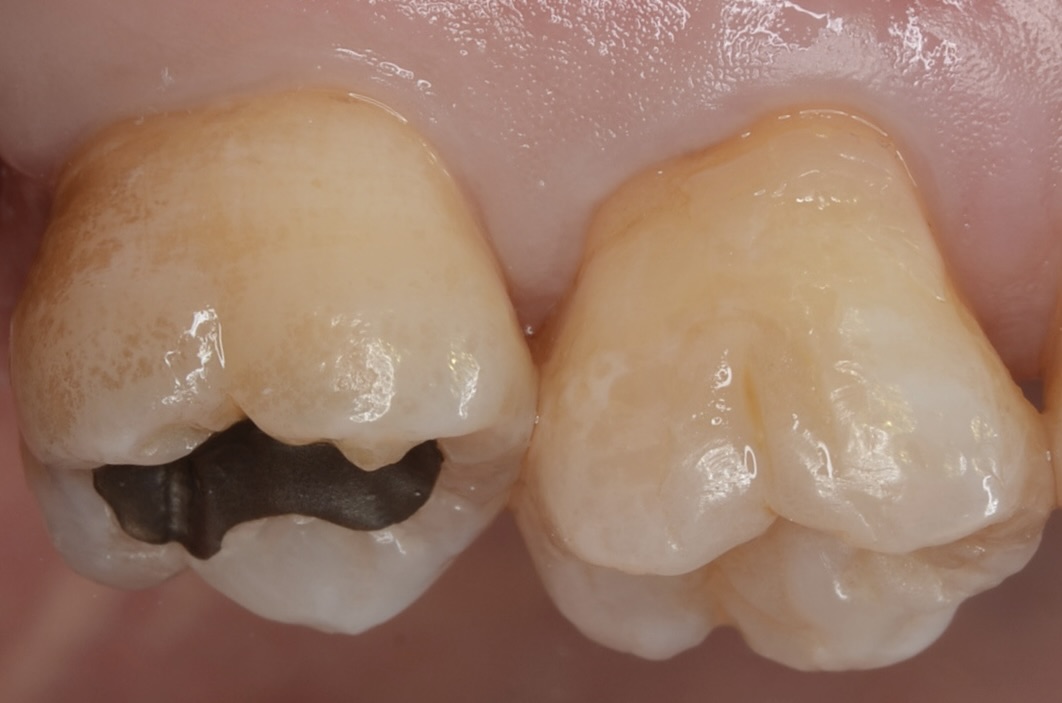

歯間離開確認

ゴムを外すと隙間ができています。そこから覗くと7番の近心に虫歯が見えます。 -

6番遠心の虫歯

6番の遠心にも虫歯が見えます。 -